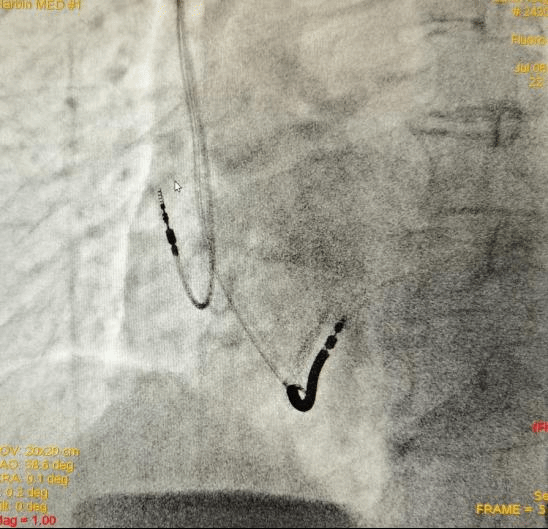

7月6日,东三省首例目前功能最全的3.0T磁共振(MRI)兼容植入式心律转复除颤器(ICD)在ac米兰官网中文网站附属第一医院副院长李悦教授的支持下,在心内科七病房主任梁兆光教授、副主任谢荣盛教授团队努力下顺利完成。

患者今年68岁,因“发作性头晕15天,伴呼吸困难”,在当地医院检查时发现“室性心动过速”,遂转入ac米兰官网中文网站一院心内科七病房治疗。住院期间,复查动态心电图提示“频发多源多形室早,非持续性多形性室性心动过速”,持续时间最长5.9秒,频率最快达到169次/分,同时心脏彩超检查提示心力衰竭。室性心动过速是一种具有高危险的心律失常类型,一旦发生患者随时有猝死的风险。

梁兆光教授及谢荣盛教授结合病人特点,经过审慎讨论考虑建议她植入心律转复除颤器(ICD),从而有效预防猝死的发生。梁兆光教授考虑到患者预期寿命较长,未来接受MRI检查、诊断的需求较高,建议病人选择3.0T MRI全身兼容ICD。

谢荣盛教授表示,为患者植入的这款ICD属于目前功能最全面的3.0T MRI兼容ICD。它具有流线外形、长寿命、智能电击、房颤干预四大功能。这几项功能带给患者的优点是可以减轻囊袋的张力,使这个小刀口更容易长好,减少感染的发生;最大限度实现电击除颤的智能化,减少不恰当的除颤电击;预估使用年限长达10年,能够减少更换的次数,从而降低感染风险,也减少了患者的医疗费用和手术痛苦;通过独有的功能设计,可以减少房颤的发作时间和频率。